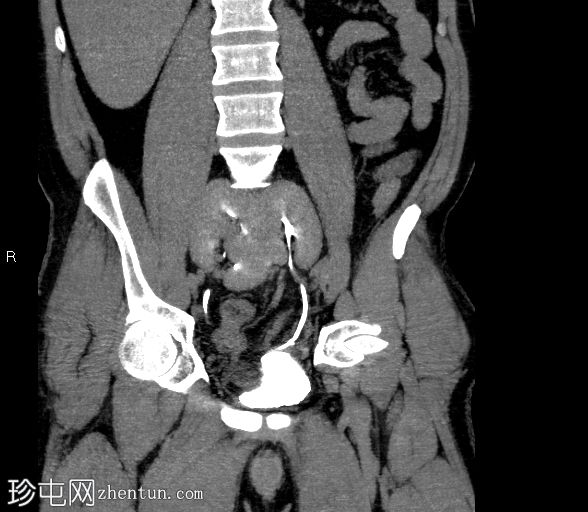

冠状位

平扫

双肾上极和下极融合,形成扁平肾,在轴位、冠状位和三维图像上均可见。

有两条独立的输尿管,左右输尿管分别独立引流至膀胱。

未见结石或反流压力改变。

本病例展示了扁平肾,这是一种解剖变异,其特征是双肾上极和下极完全融合。这与马蹄肾不同,马蹄肾仅下极通过峡部连接。

虽然扁平肾可能是一种偶然发现,但评估是否存在相关并发症(如肾结石和反复

泌尿

道感染)非常重要。